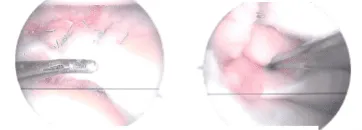

Anesthesia was administered. After applying a mid-thigh tourniquet and using chlorhexidine paint, the left lower limb was prepared. A lateral working portal was established over the left knee. The scope was entered and examination of the knee was performed.

There was patellofemoral arthritis on the medial side of the patella. There was OA grade 1 to 2 patellofemoral arthritis on the medial facet of the patella and OA grade 1 to 2 arthritis of the medial femoral condyle.

Tear in medial meniscus involving the posterior horn were repaired. The repair of the bucket-handle tear stabled by Fast-Fix. During and final pictures were taken during the operation.

Final pictures showing operative part dressed